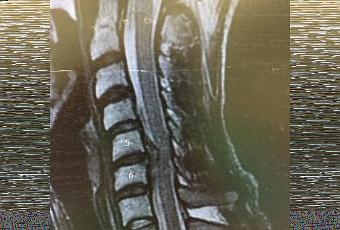

Le diagnostique est tombé ce matin (Facebook, Twitter, Instagram): hernie discale sévère entre les vertèbres C5 et C6.

Bilan: opération urgente pour retirer le disque déplacé risquant d’endommager la moelle épinière et souder ces deux vertèbres.